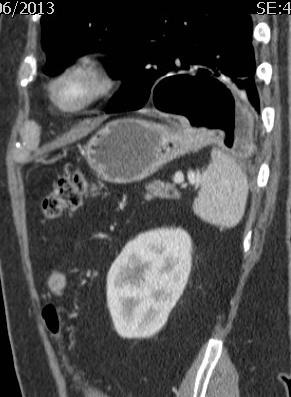

膈疝 电极通过膈肌,会有问题吗?

第三个月,在相应的膈肌部位发生变化

第九个月

胃疝出至胸腔内

膈疝2 右下肺结直肠癌转移,射频消融1年后。

膈疝(Diaphragmatic hernia)发生率<3%。主要危险因素包括,电极穿透膈肌,接触到膈肌的中间部分【5】。减少危险的方法,进行气胸、CO2、球囊间隔【6】或人工腹水(肝上部分肿瘤)【7】。 The central portion of the diaphragm